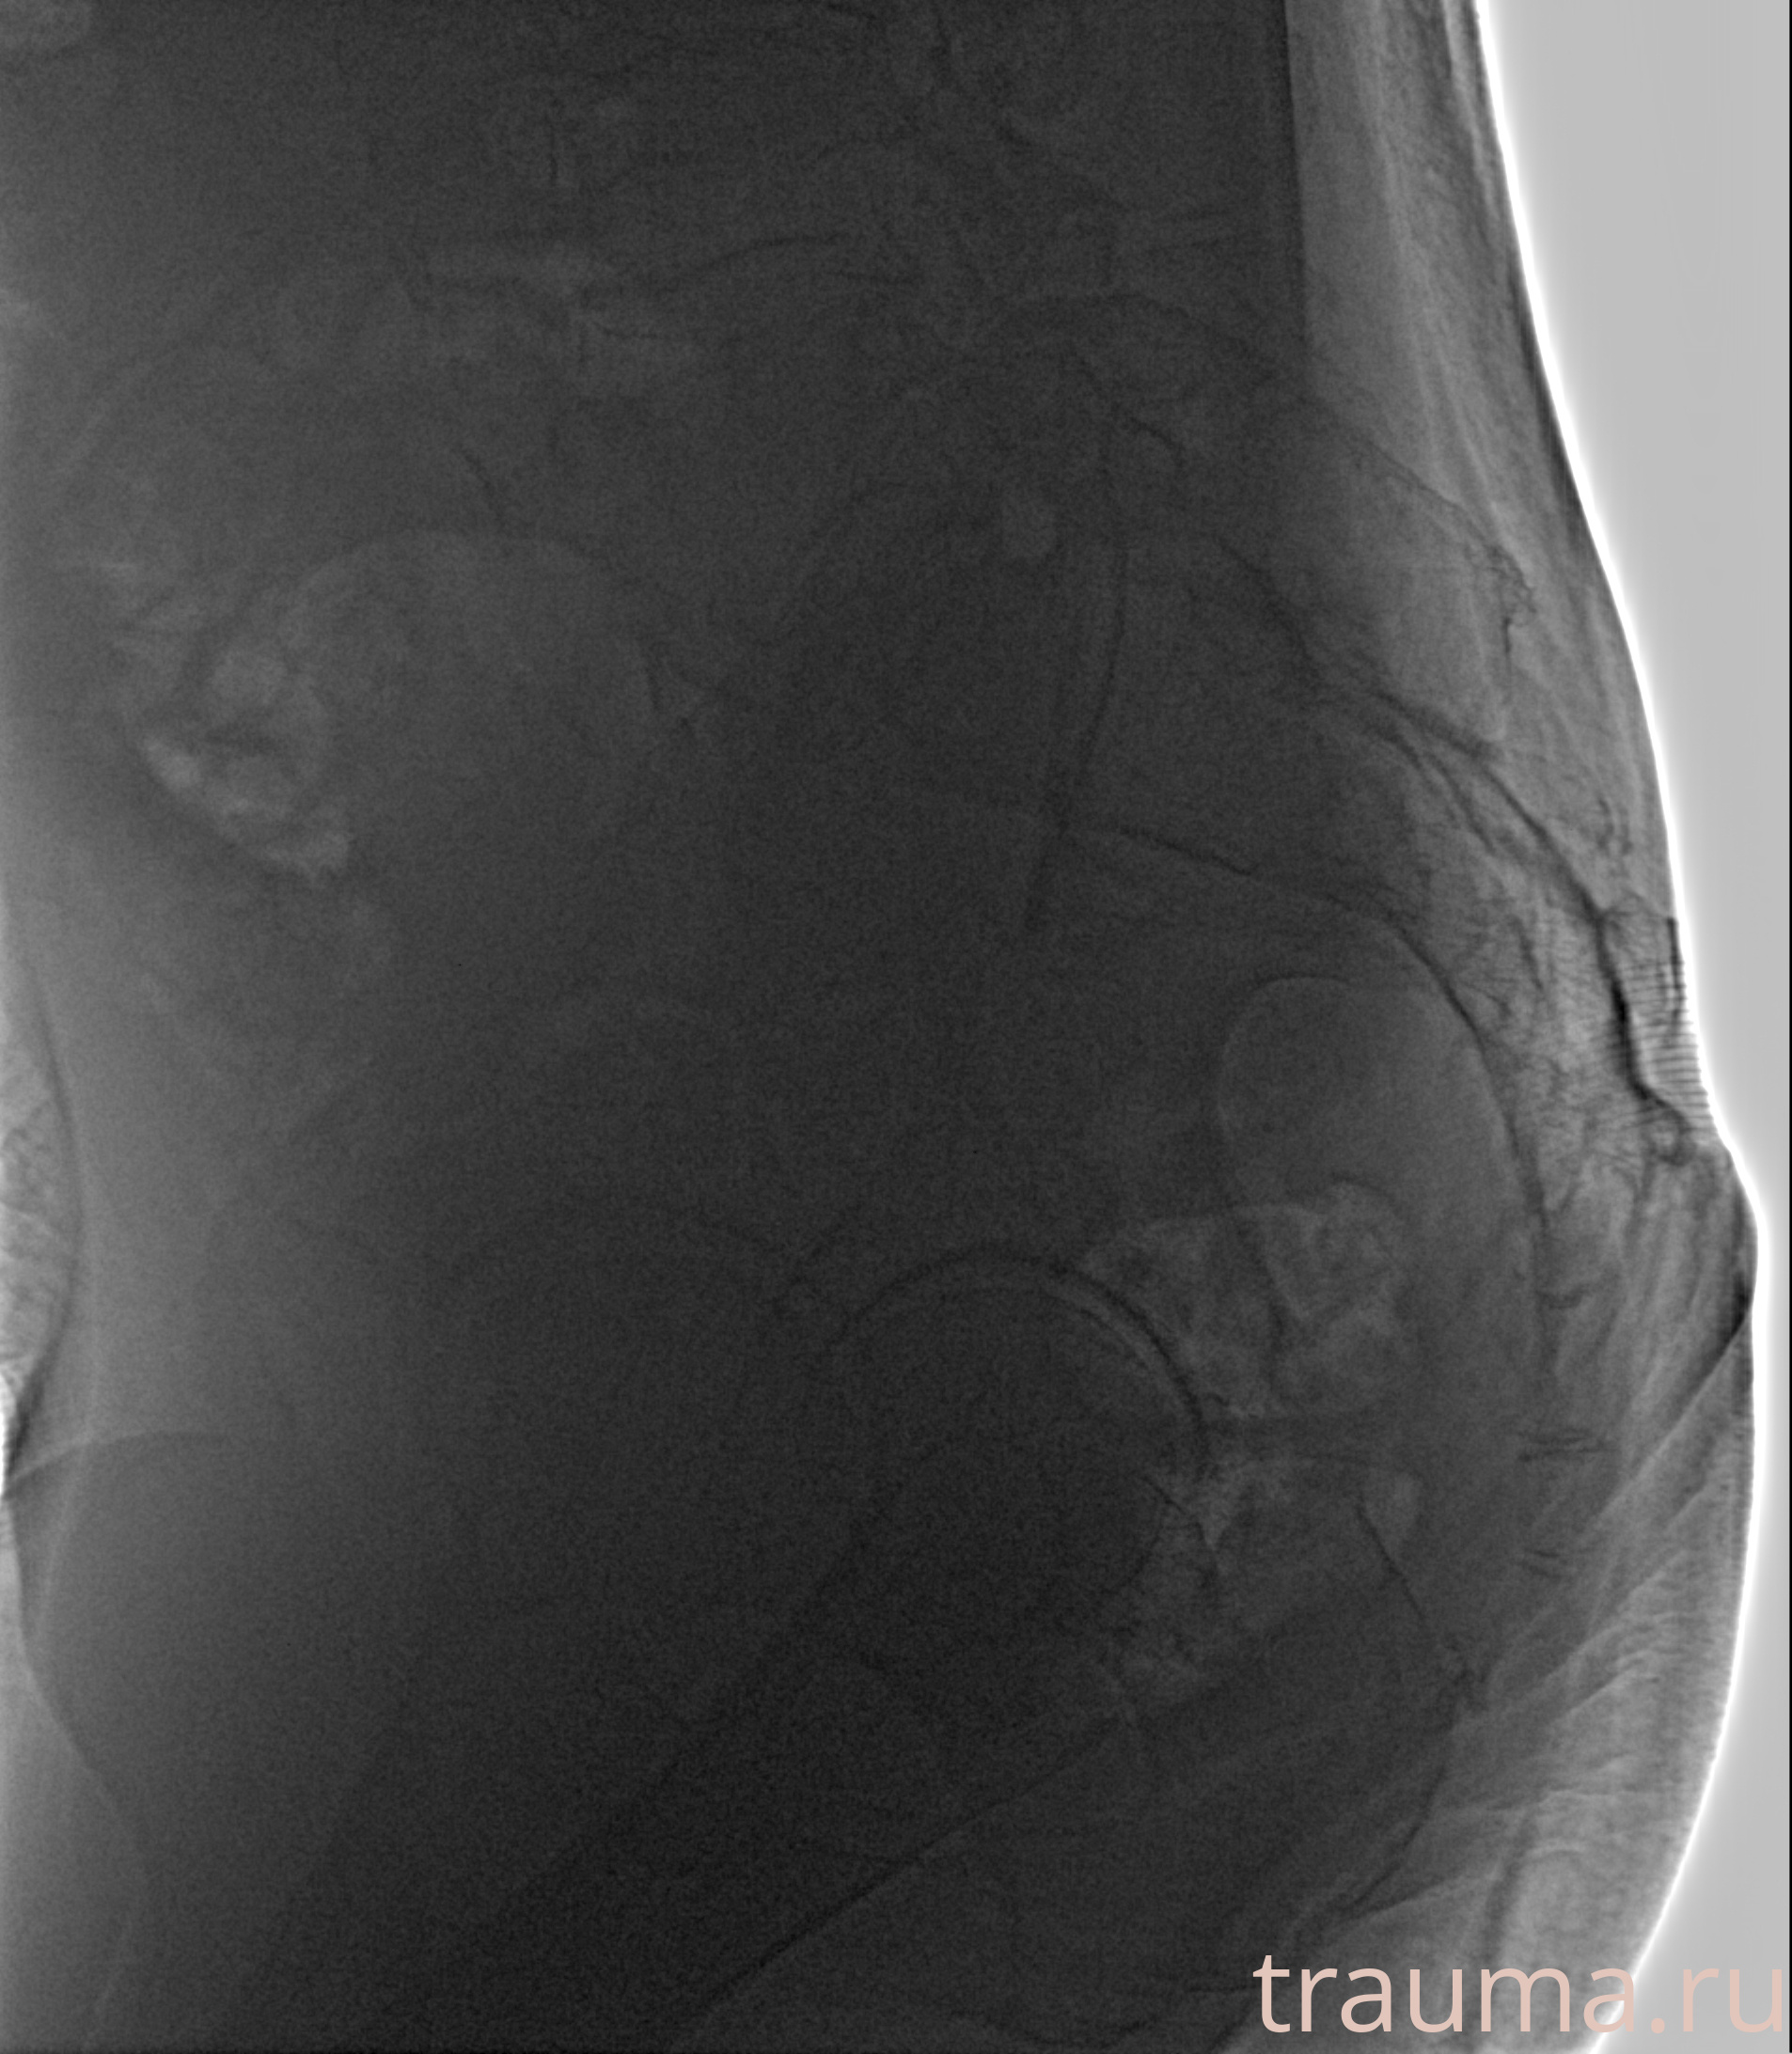

8-495-22-555-6-8при переломе шейки бедра и пневмонии от компании МосРентген Центр - партнера Института имени Склифосовскогоподробно -